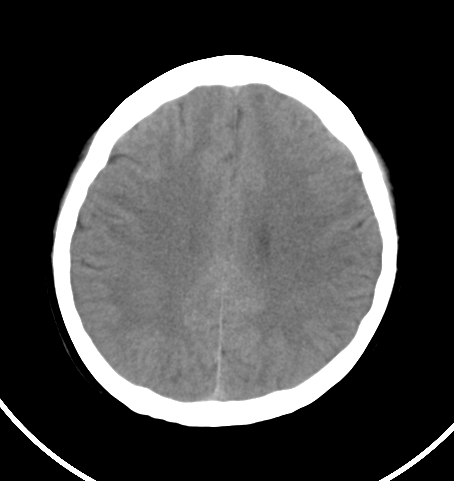

病人女 35岁 自述头晕 头痛

双侧基底节区及右侧丘脑区多发点状钙化,周围未见水肿及占位征象.余未见明显异常.考虑:脑囊虫病<囊虫的退变或死亡期>请结合有无相关病史.

未见明显异常,建议检查颈椎。